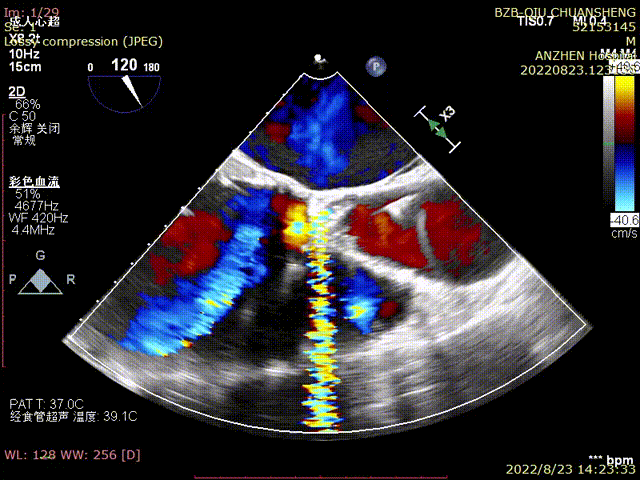

TEE-第一个TAVR后大量PVL

TTE-各大瓣膜反流(CDFI)

TTE-左室长轴-二尖瓣生物瓣+主动脉瓣生物瓣(CDFI)